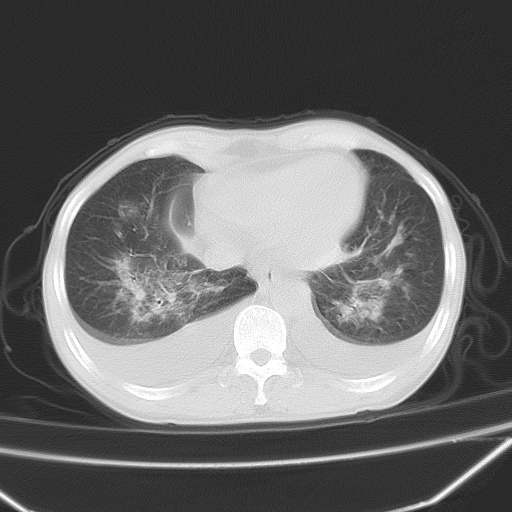

男、42岁、咯血3天。既往有甲亢、贫血、血尿蛋白尿史多年。血象:wbc:6.   中性粒:70.6%。

双肺野对称性磨玻璃影,分布于内中带,双侧胸水,患者有咯血。

双肺野广泛对称性磨玻璃影、实变影,以肺门为中心,主要分布于内中带,符合典型肺泡性肺水肿;伴双侧胸腔少量游离积液。结合患者既往病史且咯血就诊,支持多因素(尿毒症等)所致之肺水肿、肺出血、胸水;影像表现暂不考虑心源性水肿,且症状也不太符。需密切随诊结合临床治疗等进一步明确。

心影增大密度略低,双肺磨玻璃样高密度影及双侧胸腔积液,考虑心功能不全继发双肺肺水肿及双侧胸腔积液。心影密度略低,考虑贫血所致。